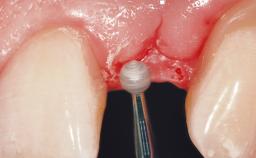

Soft Tissue Grafting Simultaneous

Soft Tissue Contour and Volume Slightly compromised